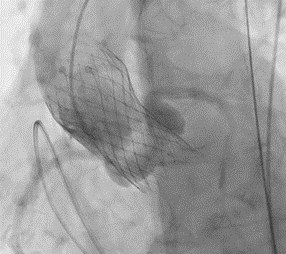

経カテーテル大動脈弁留置術(TAVI)

大動脈弁狭窄症(AS)に対し、手術で胸を開くことなく、カテーテルを用いて人工の大動脈弁を心臓に留置する治療です。

大動脈弁留置後動脈造影